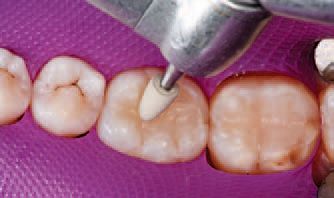

A single increment of Tetric EvoCeram Bulk Fill in shade IVA was then placed in the preparation of tooth No. 30 (Fig. 9), and shaped first with an OptraSculpt® sphere attachment (Fig. 10), then with an OptraSculpt pyramid attachment (Fig. 11). The final anatomy was contoured using a P1 plugger (Fig. 12). As a final step before finishing, the restoration was light cured with the LED curing light (Fig. 13).